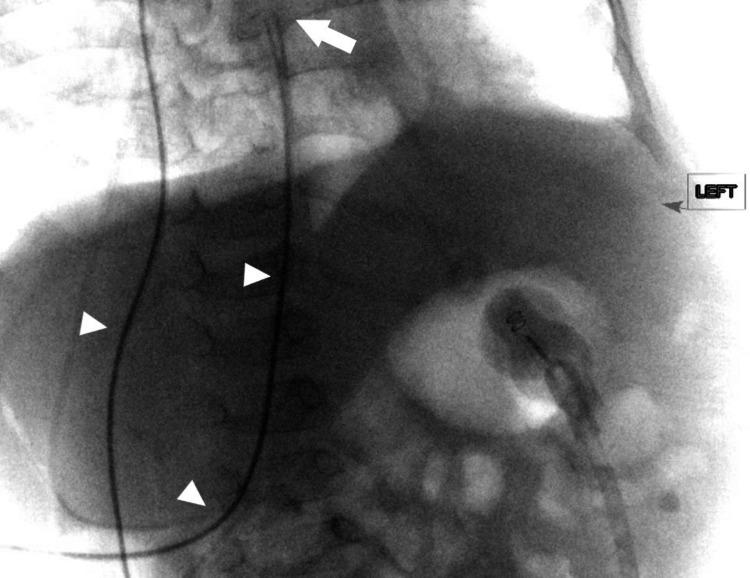

Multiple alternative sites for distal ventriculoperitoneal shunts have been described including pleural, atrial, ureteral, fallopian, and gallbladder placement. In medically complex patients the sites for cerebrospinal fluid (CSF) diversion can be exhausted. We present a case where open retroperitoneal inferior vena cava cannulation was used for successful atrial catheter placement in a 17-month-old female. The patient had a complex abdominal, pulmonary, and vascular history precluding placement of the distal catheter in other sites or atrial placement through more peripheral venous cannulation. The patient underwent uncomplicated open retroperitoneal exposure of her inferior vena cava (IVC) with cannulation and placement of atrial catheter under fluoroscopic guidance. At the follow-up one year after surgery, the patient did not require revision with appropriate placement of the distal atrial catheter.

已经描述了多种用于远端脑室腹腔分流术的替代部位,包括胸膜、心房、输尿管、输卵管和胆囊置入。在病情复杂的患者中,脑脊液(CSF)分流的部位可能会用尽。我们报告了一例17个月大的女性患者,通过开放腹膜后下腔静脉插管成功进行心房导管置入。该患者有复杂的腹部、肺部和血管病史,排除了在其他部位放置远端导管或通过更外周静脉插管进行心房置入的可能性。患者在透视引导下接受了简单的开放腹膜后下腔静脉(IVC)暴露,并进行了插管和心房导管置入。术后一年随访时,患者远端心房导管位置合适,无需翻修。